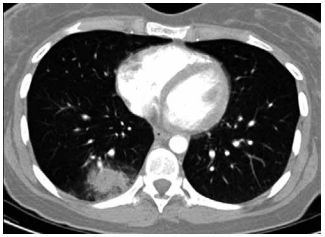

Mulher de 72 anos é atendida em consulta de retorno. O

histórico é positivo para tabagismo de 25 anos-maço e

DPOC (grau 3; grupo B). Recentemente, ela teve pneumonia com infiltrado persistente no lobo inferior direito

observado na radiografia de tórax. A paciente foi tratada

com antibiótico. Seu peso permaneceu estável, e ela não

apresentou febre ou sudorese noturna. Após seis semanas, uma radiografia de tórax de acompanhamento não

apresentou alterações. Uma tomografia é então realizada

e mostrada a seguir (a parte sólida do nódulo é de 7 mm):